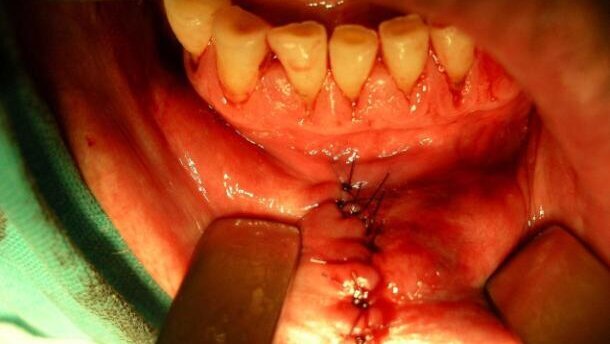

W badaniu klinicznym stwierdzono owrzodzenie o Ø ok. 10 mm, wyniesione ponad poziom czerwieni wargowej i otoczone wałowatym brzegiem (Ryc. 1). Węzły chłonne podbródkowe, podżuchwowe i szyjne nie były podejrzane klinicznie. Wykonano badania dodatkowe. Pobrany wycinek do badania histopatologicznego potwierdził podejrzenie raka płaskonabłonkowego. W badaniu ultrasonograficznym szyi i okolicy nadgnykowej nie stwierdzono powiększenia węzłów chłonnych. Badania: rtg pantomograficzne i klatki piersiowej – bez zmian patologicznych. Także ultrasonografia jamy brzusznej nie wykazała zmian patologicznych. Ustalono rozpoznanie: Carcinoma planoepitheliale labii inferioris ad lateris sin.(T1N0M0).Zaplanowano usunięcie zmiany z marginesem zdrowych tkanek. Zabieg wykonano na życzenie pacjenta w znieczuleniu ogólnym z intubacją (Ryc. 2). Przeprowadzono klinowate wycięcie guza w zakresie pełnej grubości wargi z marginesami bocznymi 5 mm i głębokim 10 mm (Ryc. 3-4).

Badanie histopatologiczne intra operationem potwierdziło charakter nowotworu i nie wykazało obecności komórek raka w marginesach tkankowych. Ranę zaopatrzono warstwowo (błona śluzowa – szwy polidioksanon 4-0, warstwy wewnętrzne – kwas glikolowy 4-0, czerwień i skóra wargi – nylon 6-0, Ryc. 5-6). Całość materiału została poddana ostatecznemu badaniu histopatologicznemu. Wynik: Carcinoma planoepitheliale exulcerans (Ryc. 7-9). Gojenie pooperacyjne przebiegało bez powikłań, szwy usunięto w 7 dobie po zabiegu. Następnie wg wskazań lekarza onkologa zalecono profilaktyczną radioterapię okolicy operowanej oraz regionu nadgnykowego i szyi celem ewentualnego wyeliminowania mikroognisk nowotworu, pomimo klinicznie niepodejrzanych węzłów chłonnych.